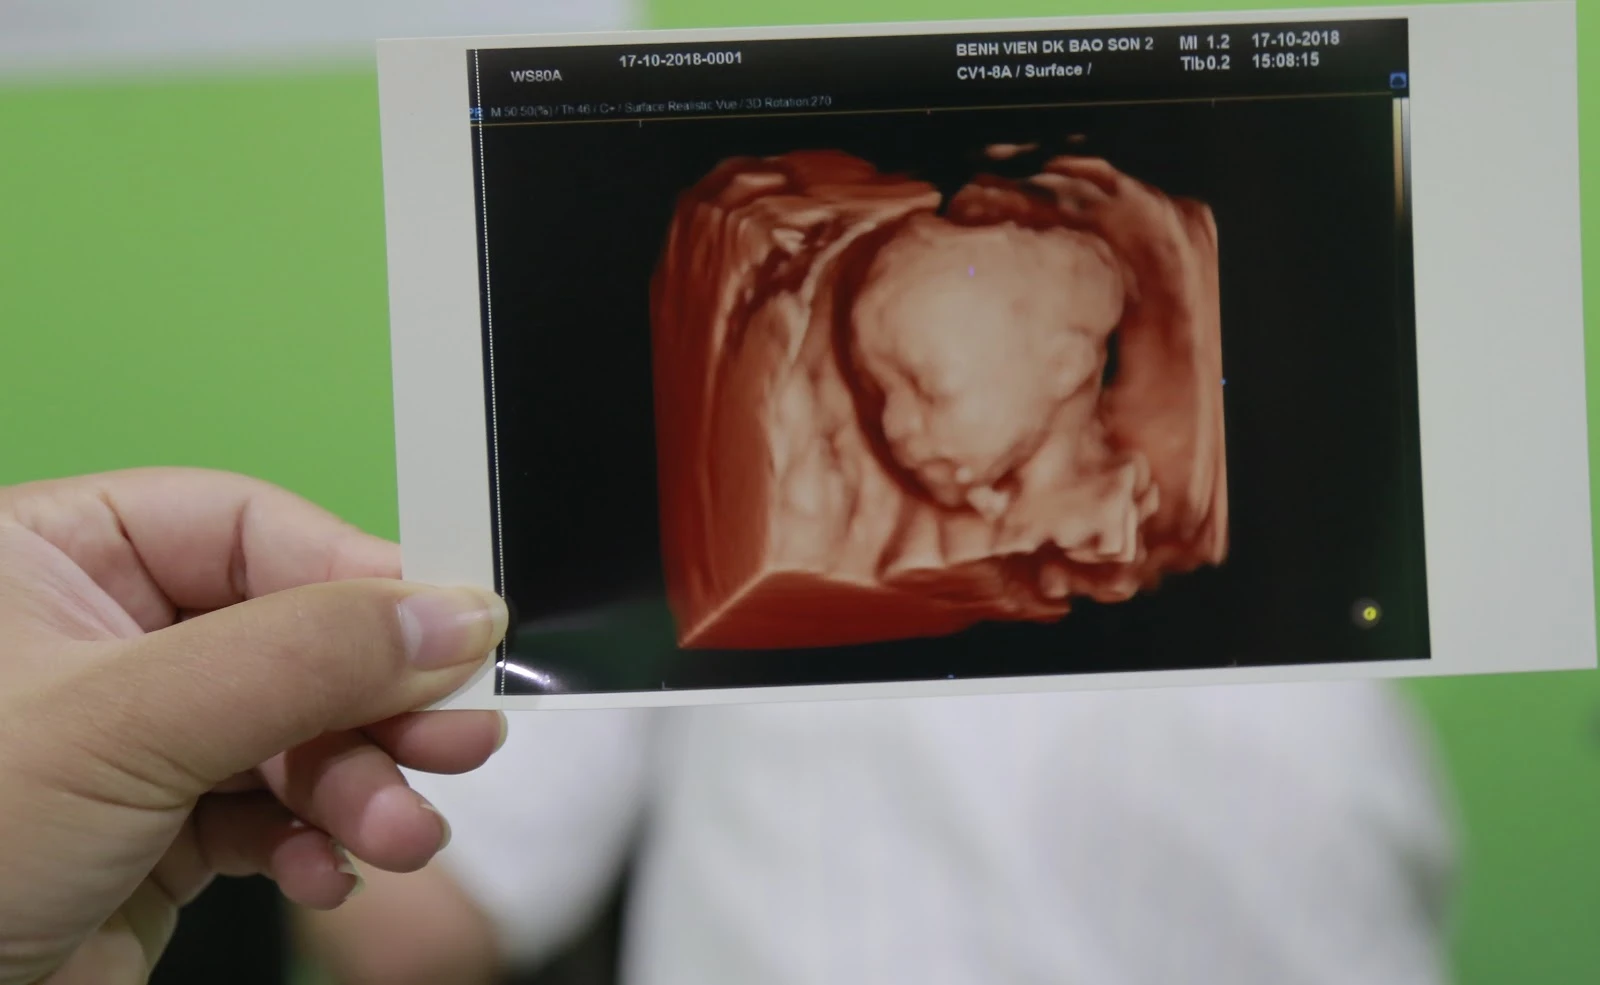

Siêu âm hình thái thai nhi là một kỹ thuật chẩn đoán hình ảnh quan trọng trong quá trình theo dõi thai kỳ, giúp đánh giá chi tiết cấu trúc và sự phát triển của thai nhi. Với những bậc phụ huynh đang chuẩn bị cho hành trình làm cha mẹ, việc hiểu rõ tầm quan trọng của siêu âm hình thái là vô cùng cần thiết. Công nghệ siêu âm ngày nay cho phép các bác sĩ nhìn sâu vào bên trong để kiểm tra từng chi tiết nhỏ nhất, từ não, tim, các cơ quan nội tạng tới khung xương của bé, đảm bảo phát hiện sớm các dị tật bẩm sinh. Cảm giác kỳ diệu khi lần đầu tiên nhìn thấy hình ảnh con yêu trên màn hình là khoảnh khắc không thể quên đối với nhiều phụ huynh, nó như mở ra cánh cửa để kết nối với thế giới bên trong của thai nhi. Các dị tật lớn thường có thể phát hiện sớm thông qua siêu âm, giúp bác sĩ và gia đình có những quyết định thông minh và kịp thời trong việc chăm sóc sức khỏe cho cả mẹ và con.

Siêu âm hình thái thai nhi là phương pháp không xâm lấn sử dụng sóng siêu âm tần số cao để tạo ra hình ảnh chi tiết về cấu trúc cơ thể thai nhi. Phương pháp này không chỉ giúp xác định kích thước và trưởng thành của tam thể tích thai nhi mà còn giúp bác sĩ quan sát và phân tích các bộ phận cơ quan một cách rõ ràng. Nhiều nghiên cứu y học đã chỉ ra rằng, thực hiện đầy đủ các đợt siêu âm hình thái có thể tăng cường tỷ lệ phát hiện sớm các dị tật như dị dạng tim, cấu trúc xương hoặc các vấn đề nhiễm sắc thể. Những hình ảnh rõ nét từ máy siêu âm như mở ra một bức tranh sống động về cuộc sống của thai nhi bên trong bụng mẹ, cho phép bác sĩ đưa ra những đánh giá chính xác và kịp thời nhất.

Đặc biệt, trong hành trình mang thai, siêu âm hình thái là một phần không thể thiếu trong các đợt kiểm tra định kỳ. Với những bà mẹ lần đầu trải nghiệm, đây thực sự là một trải nghiệm đầy xúc động. Những khoảnh khắc nhìn thấy con yêu đang "nhảy múa" trong bụng mẹ, thấy từng nhịp tim đập hay tay chân đang co duỗi là những ký ức vô giá. Như một bức tranh y khoa riêng biệt, mỗi hình ảnh siêu âm không chỉ phản ánh sự phát triển của thai nhi mà còn mang lại tâm lý yên tâm cho bà mẹ trẻ khi biết con mình đang phát triển khỏe mạnh.